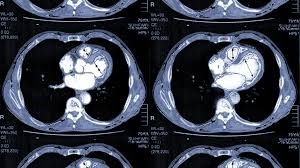

HRCT

A High-Resolution Computed Tomography (HRCT) scan is a non-invasive, specialized imaging test using thin slices (1–2 mm) and high-spatial-frequency algorithms to provide detailed, high-definition images of lung tissue (parenchyma).